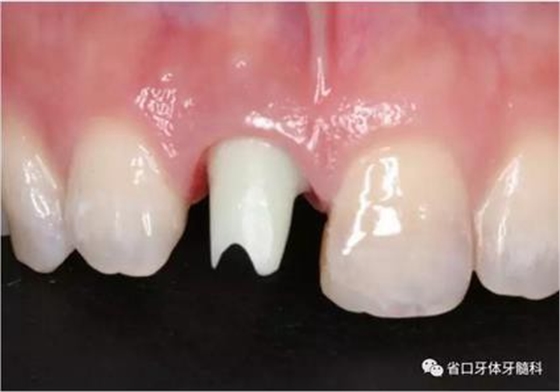

圖1 術(shù)前口內(nèi)照

圖2 術(shù)前口內(nèi)照

圖3 術(shù)前口內(nèi)照

(1)微創(chuàng)拔牙及即刻種植:術(shù)前拍攝口內(nèi)照及實(shí)施牙周基礎(chǔ)治療。常 規(guī)消毒鋪巾阿替卡因局麻下微創(chuàng)拔除上頜右側(cè)中切牙,搔刮拔牙窩及根尖肉 芽組織。探測牙槽骨唇側(cè)骨壁及鄰面牙槽嵴完整,牙齦無撕裂。不翻瓣下于上頜右側(cè)中切牙缺隙近遠(yuǎn)中中點(diǎn)的腭側(cè)牙槽骨及根方定位,按照逐級預(yù)備的原則,緊貼牙槽窩腭側(cè)骨壁制備種植窩洞,植入Zimer®3.7mm×13mm TSV種植體1顆,植入扭矩>35N·cm,以O(shè)sstell測量種植體的ISQ值為68。 種植體平臺位于唇側(cè)齦緣中點(diǎn)下3mm,與唇側(cè)骨壁內(nèi)側(cè)面形成的跳躍間 隙約2mm,置入Bio-Oss®細(xì)顆粒骨粉0.25g,上愈合基臺關(guān)閉創(chuàng)口。術(shù)后 CBCT檢查顯示:種植體利用牙槽窩根方骨質(zhì)固位,緊貼牙槽窩腭側(cè)骨壁, 其唇側(cè)面與牙槽窩唇側(cè)骨壁的內(nèi)側(cè)面所形成的跳躍間隙(約2mm)可見顆 粒狀顯影物充填。牙槽窩的唇側(cè)骨壁及唇側(cè)倒凹無缺損穿孔。